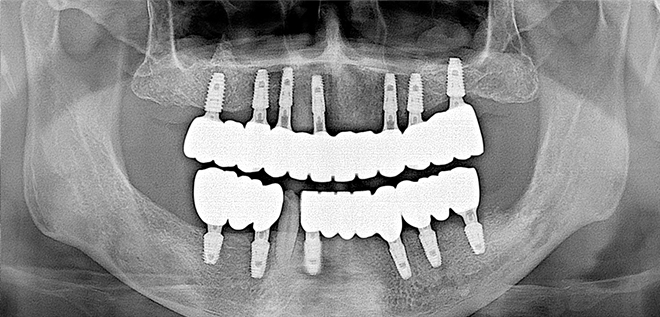

Before & After

어려운 임플란트 시술도

남양바른탑에서는 가능합니다.